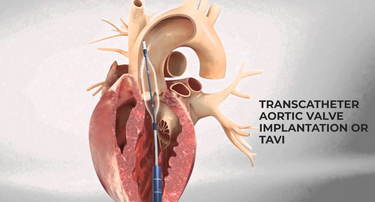

TAVI Vs. Open-Heart Surgery: Which Is The Right Choice For You?

For heart valve replacement, patients usually have two primary choices: Transcatheter Aortic Valve Implantation (TAVI) and open-heart surgery. Both involve replacing a faulty aortic valve, but they are very different in approach, recovery period, and applicability to various patient populations. Knowing the main differences, advantages, disadvantages, and success rates can assist you in making an informed choice.

Who Is The Ideal Candidate For TAVI? Understanding Eligibility & Benefits

Transcatheter Aortic Valve Implantation (TAVI) has revolutionized the treatment of severe aortic stenosis, especially for patients who are high-risk candidates for traditional open-heart surgery. This minimally invasive procedure offers a lifeline to many, but determining who stands to benefit the most is crucial.